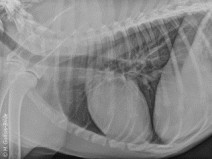

• Travaux pratiques de radiographie / Le Thorax

Formation complète

Le GEIM vous propose une séance de travaux pratiques de radiographies sur le thorax. Tous les aspects sont abordés sous la forme de TP de lecture de radiographies numériques sur station de travail Osirix sur tablettes.